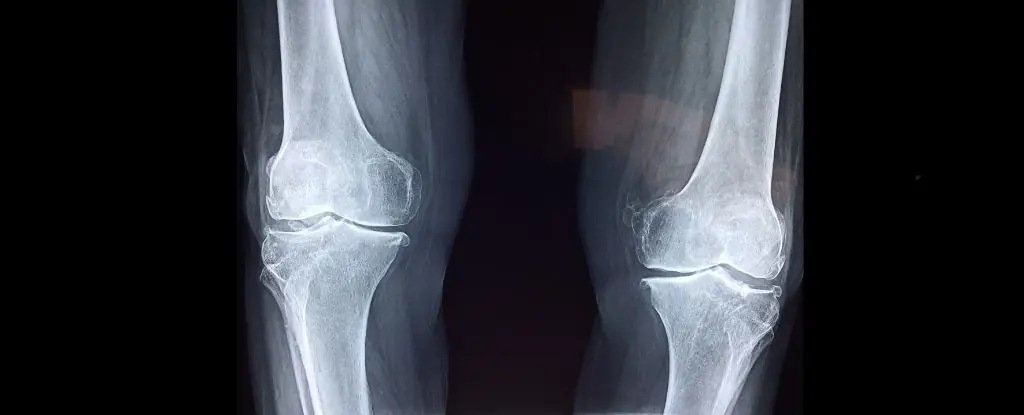

Osteoporosis is frequently referred to as a “silent killer,” and for good reason. Unlike many illnesses that show clear warning signs early on, osteoporosis progresses quietly over many years, weakening the bones without causing noticeable symptoms. By the time most people discover they have it, significant bone loss has already occurred—and sometimes the first sign is a serious fracture. This is why early awareness, prevention, and timely management are essential. Understanding how osteoporosis works, who is at risk, and why it is so dangerous can help individuals take proactive steps to protect their bone health.

Bones are living tissues that constantly break down and rebuild. When we are young, our bodies create new bone faster than they break it down, allowing our bone density to increase. However, as we age—especially after age 40—bone loss starts to occur more rapidly. In osteoporosis, this natural process becomes imbalanced: bones lose density at a much faster rate than the body can replace it.

Because this process happens internally and progresses slowly, people usually feel no pain. There are no headaches, no fevers, no sharp alarms—only quiet bone thinning. This is why osteoporosis is often not discovered until a bone breaks from what seems like a minor fall, or even from simple movements such as bending, coughing, or lifting something light.